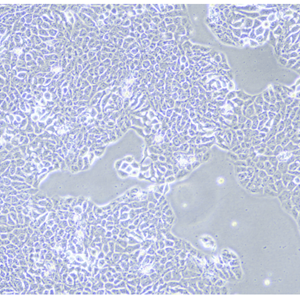

产品信息: